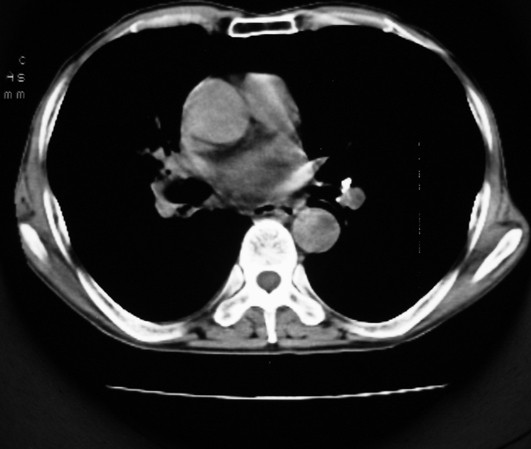

以下是引用同在2007-1-27 14:13:00的发言:[br]支持右侧中央型肺癌伴阻塞性病变.

以下是引用zjzjr在2007-1-27 16:56:00的发言:[br]支持右肺中心型肺癌伴阻塞性肺炎.